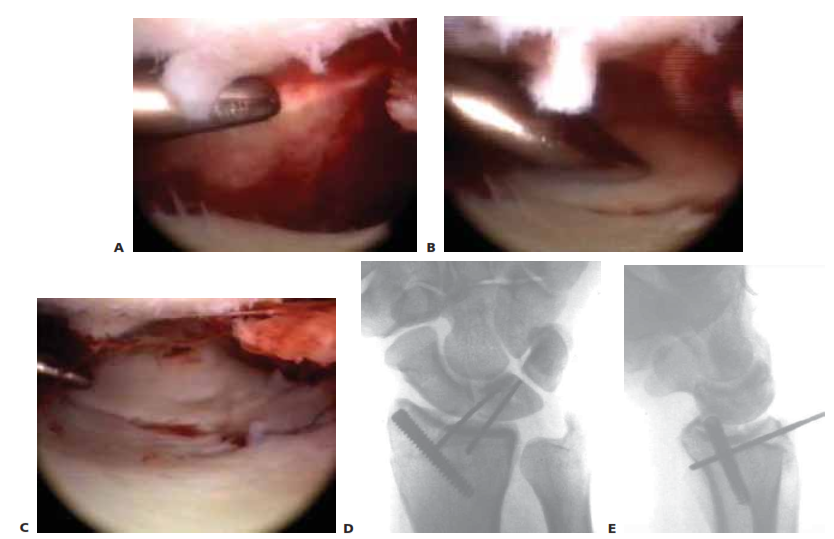

Arthroscopic Reduction and Fixation of Distal Radius and Ulnar Styloid Fractures DEFINITION ■ A bimodal ag…

RADIAL STYLOID FRACTURES ■ An isolated fracture of the radial styloid is an ideal fracture patte…